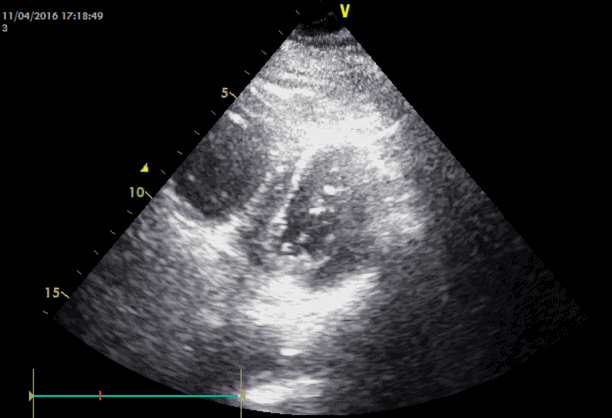

Emergency transesophageal echocardiography (TEE) was performed. The test revealed a hypokinetic dilated right ventricle (RV) and a D-shaped left ventricle (LV) (Figure 2). LV systolic dysfunction was noted without inferior vena cava (IVC) collapsibility. Tricuspid regurgitation was found with 49 mmHg pressure gradient (Figure 3). Considering the decreased EtCO2, elevated PaCO2, and TEE findings, PTE was suspected. Cardiopulmonary resuscitation until return of spontaneous circulation was repeated 3 times. HR was maintained at 120 beats/min, SBP at 150 mmHg, and SpO2 at 70%. Following consultation with cardiology and neurosurgery, we decided to use thrombolytics after diagnosis by multidetector computed tomography (MDCT). MDCT revealed occlusion of both pulmonary arteries with multiple pulmonary thromboembolisms and atelectasis in both lungs, consistent with a diagnosis of acute PTE (Figure 4). DVT was not observed elsewhere. The D-dimer level from a sample obtained in the operating room was above 3,200 ng/ml and troponin I was 0.02 ng/ml.